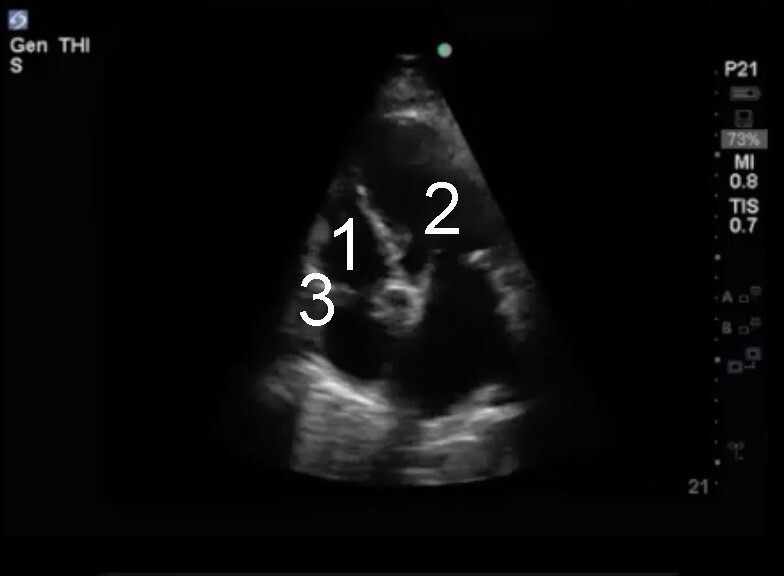

Cardiac 2 Anatomic Orientation to the RV and the Apical 4 Chamber View Image

1. Right Ventricle (RV)

2. Left Ventricle (LV)

3. Tricuspid Annulus